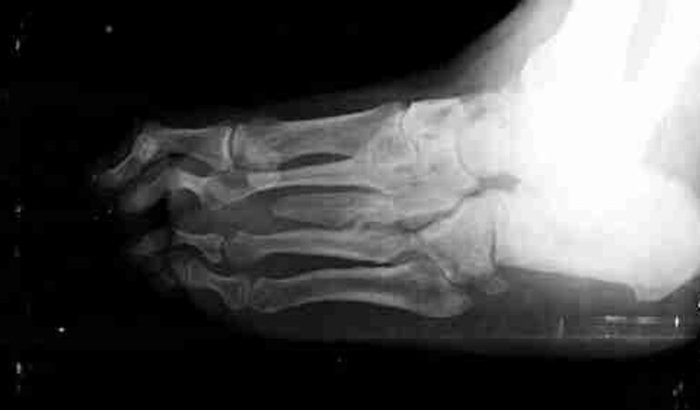

Sou diabético e desde 2019 luto contra uma infecção que se desenvolveu no meu pé direito, chamada doença de Charcot. Essa doença é uma infecção, que fica alojada dentro dos ossos, o que torna os antibióticos ineficazes. A mesma vai corroendo os ossos até o ponto de ter que amputar o membro. Além disso, a doenca acabou com toda a cartilagem entre a tíbia e o pé. Isso causa dores horríveis e inchaços.

A cirurgia vai repor essa cartilagem, e raspar os ossos, pra tentar evitar a amputação.